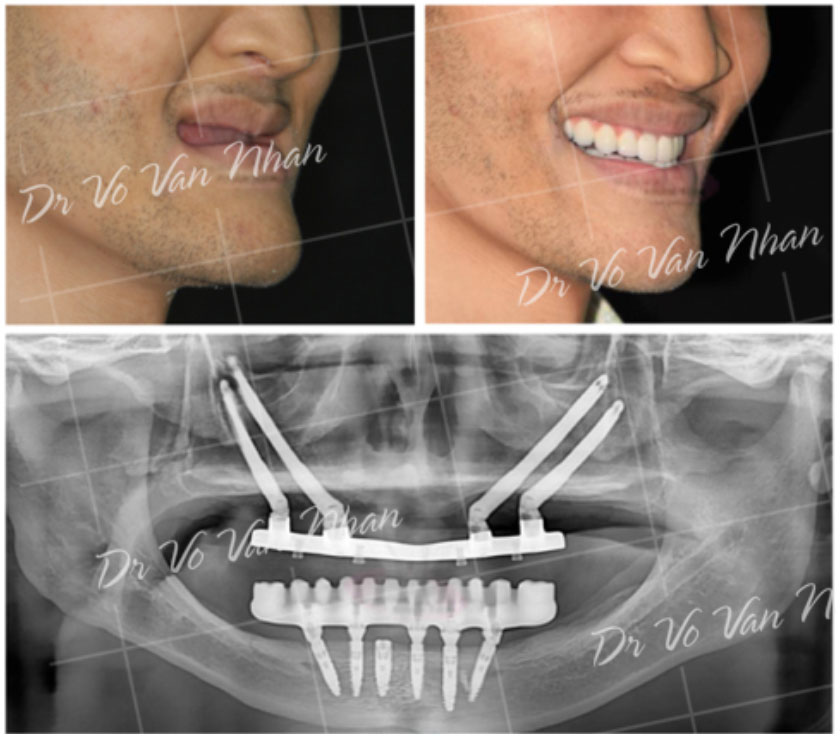

Điều trị bệnh nhân không răng bẩm sinh (*)

(*) Các thủ thuật/phẫu thuật phức tạp sẽ được chuyển đến bệnh viện để thực hiện